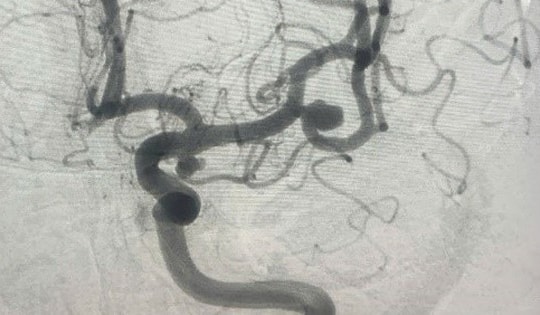

Đau đầu âm ỉ, người đàn ông 58 tuổi ở Hà Nội suýt vỡ mạch máu não vì căn bệnh này

GĐXH – Sau 2 tuần bị đau đầu, uống thuốc không đỡ, ông D đến viện được phát hiện bị phình mạch máu não, có khả năng vỡ cao.